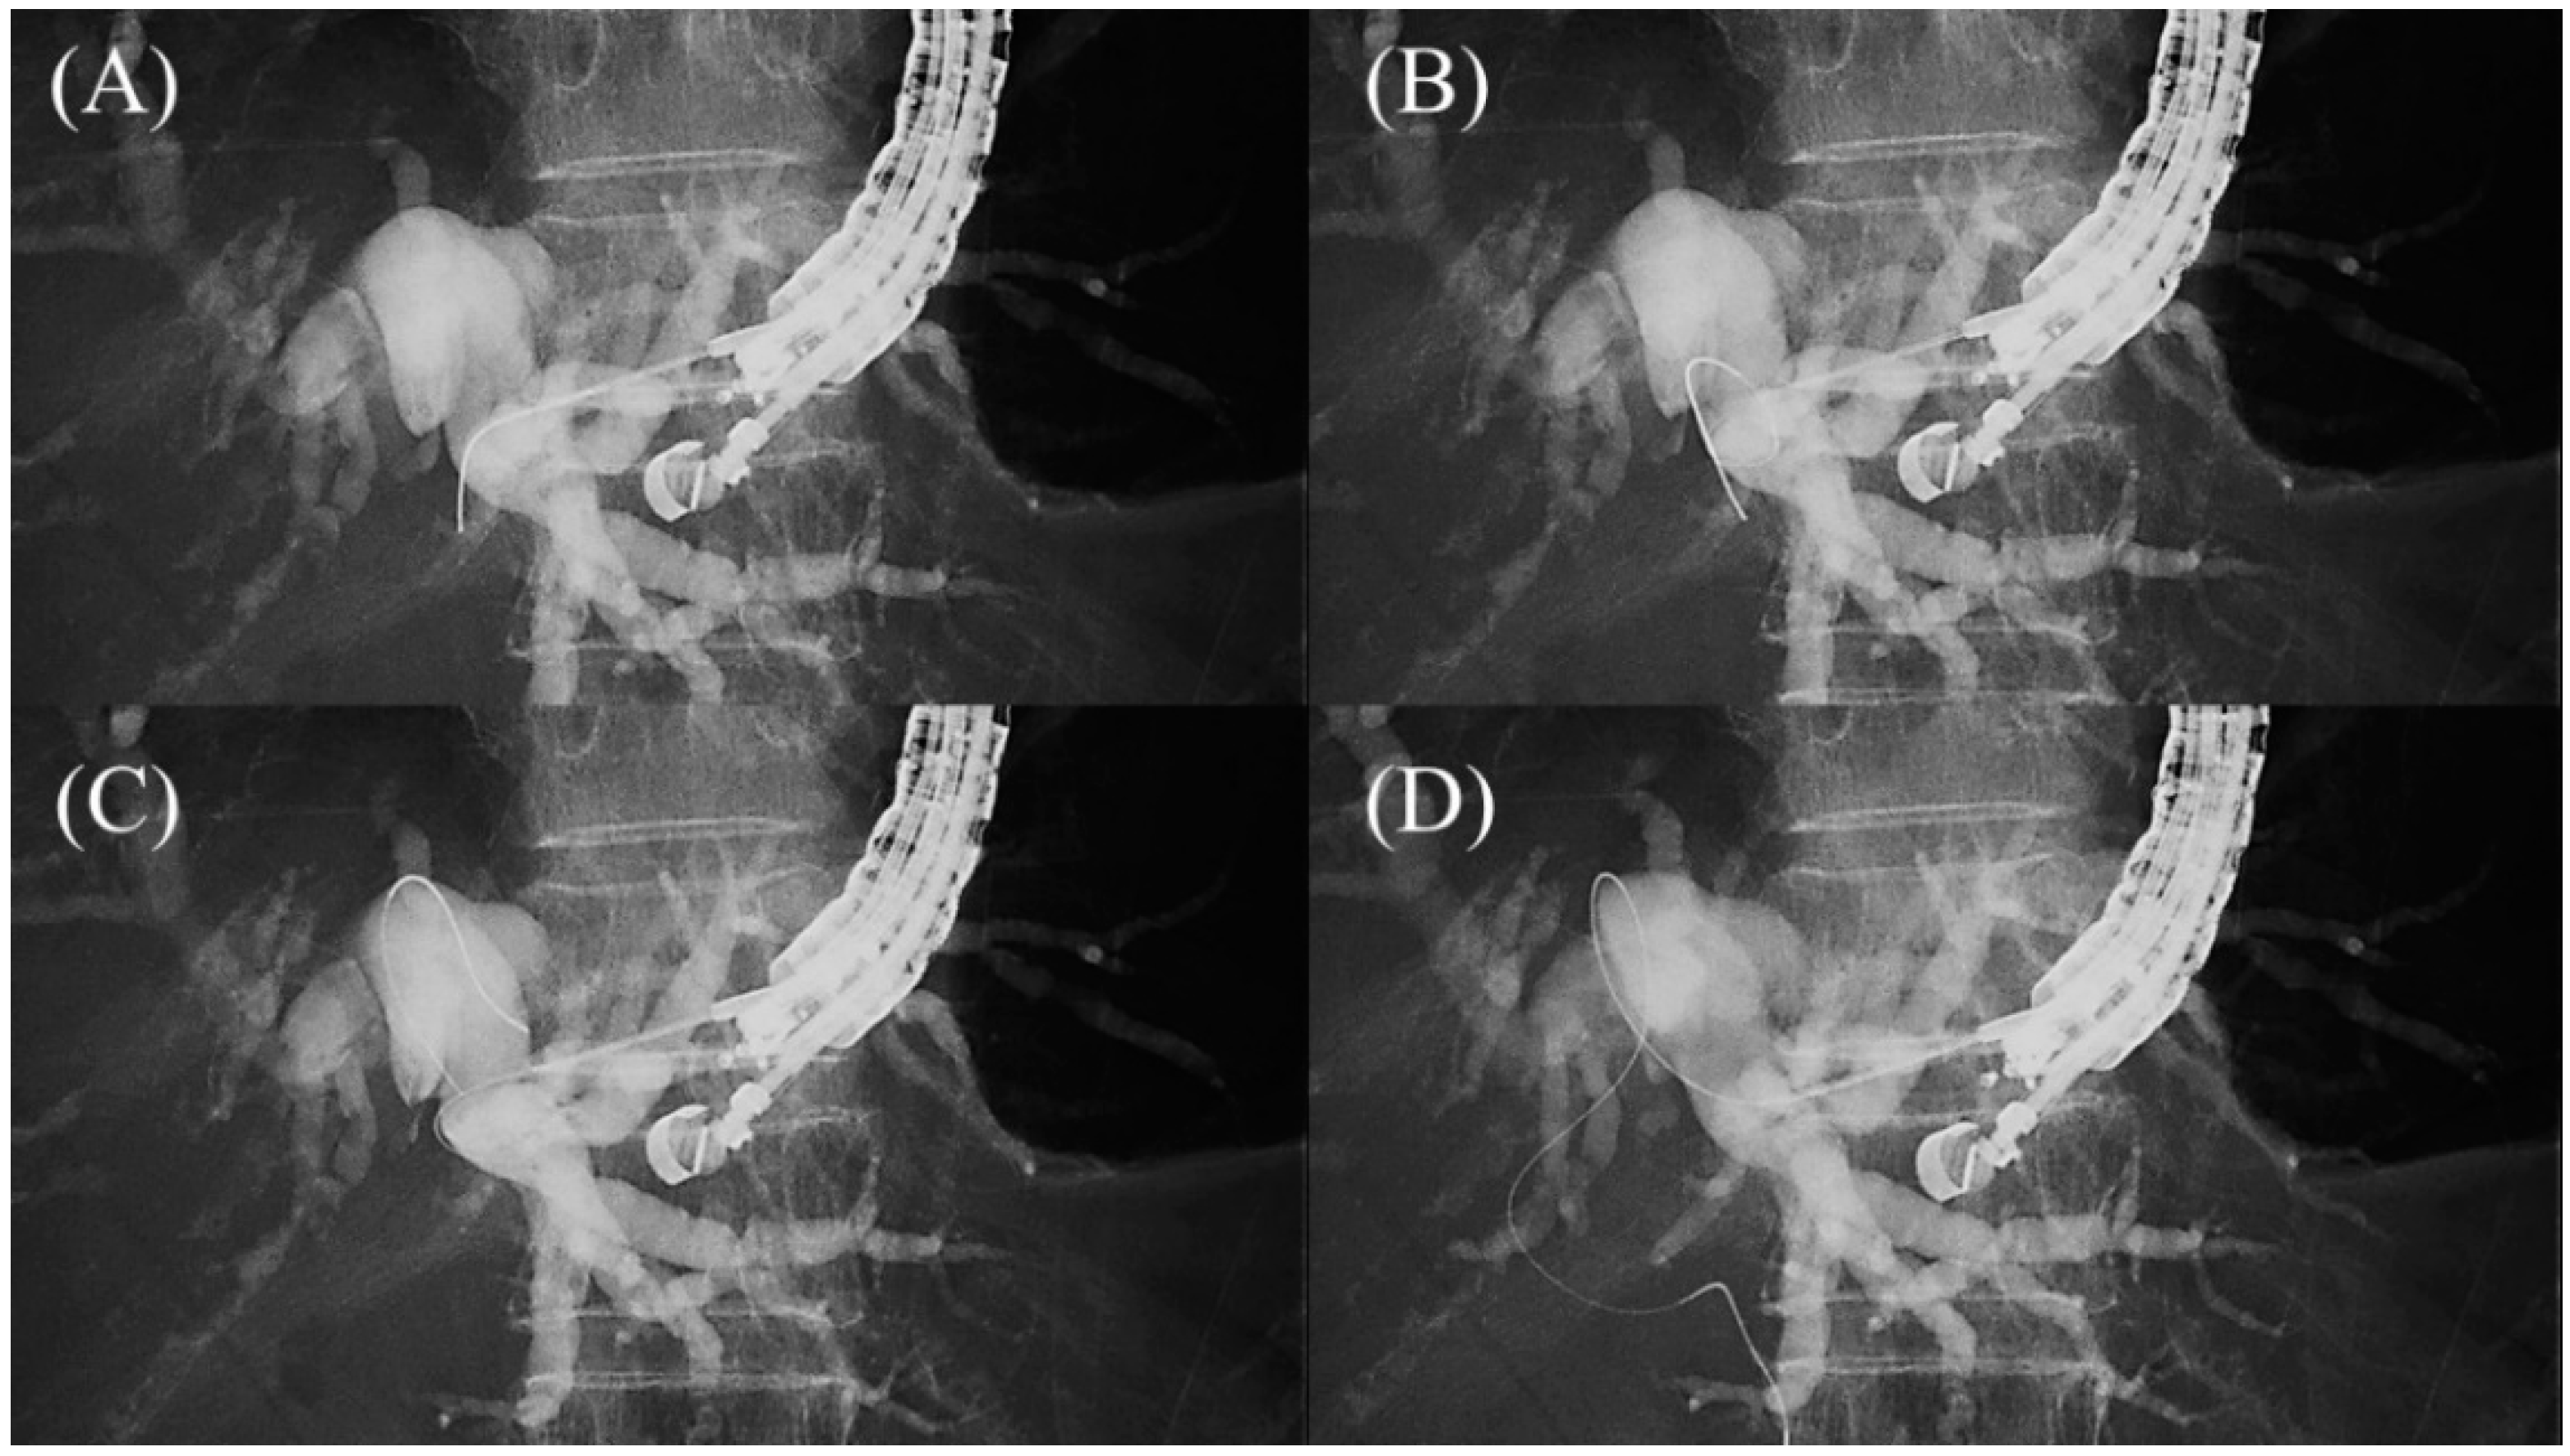

- Paik, W.H.; Park, D.H.; Choi, J.H.; Choi, J.H.; Lee, S.S.; Seo, D.W.; Lee, S.K.; Kim, M.H.; Lee, J.B. Simplified fistula dilation technique and modified stent deployment maneuver for EUS-guided hepaticogastrostomy. World J. Gastroenterol. 2014, 20, 5051–5059. [Google Scholar] [CrossRef]